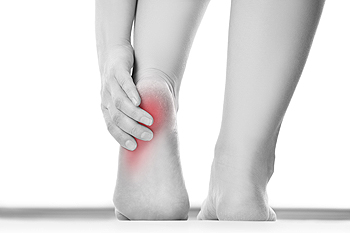

Heels spurs are often defined as a buildup of calcium deposits that form on the underside of the heel bone. When the foot muscles or ligaments are inflamed or strained, a heel spur may develop. Heel spurs can be particularly painful when partaking in activities such as walking, running, or jogging. To help care for a heel spur, it’s suggested that the affected foot is regularly rested and iced. Performing stretches before getting out of bed, wearing properly fitted shoes as well as inserts, and maintaining a healthy weight, can all benefit in relieving the discomfort of a heel spur. In order to treat this condition, it’s suggested you seek the professional care of a podiatrist.

Heel spurs can be incredibly painful and sometimes may make you unable to participate in physical activities. To get medical care for your heel spurs, contact one of our podiatrists from Advanced Foot & Ankle Medical Center . Our doctors will do everything possible to treat your condition.

The pain associated with spurs is often because of weight placed on the feet. When someone is walking, their entire weight is concentrated on the feet. Bone spurs then have the tendency to affect other bones and tissues around the foot. As the pain continues, the feet will become tender and sensitive over time.